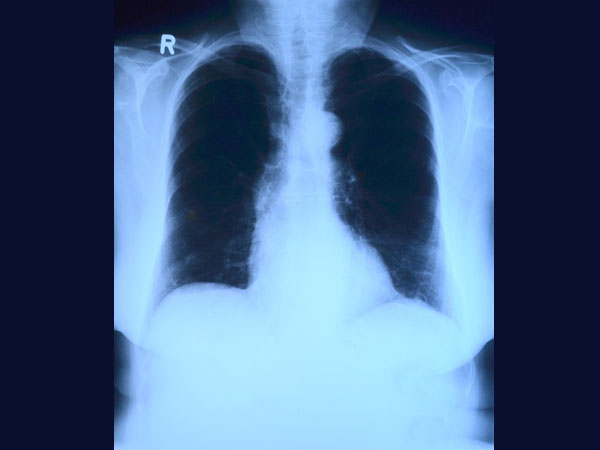

എക്സ്-റേ എന്ന ഭീകരന്

നമ്മള് അറിയാതെയാണെങ്കിലും എക്സ്-റെ എന്ന ഭീകരനെ പലപ്പോഴും ജീവിതത്തില് ആശ്രയിക്കുന്നു. ചെറിയ ചെറിയ പരിക്കുകള്ക്ക് പോലും എക്സ്-റെ എടുക്കുന്നത് ക്യാന്സര് ഉണ്ടാക്കുന്നു എന്ന കാര്യത്തില് സംശയമില്ല.